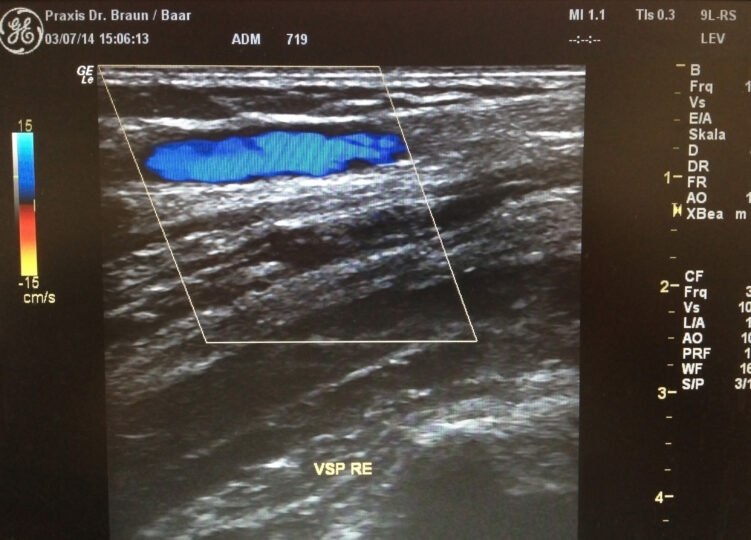

Unter Thrombose versteht man einen Verschluss einer Vene aufgrund eines Blutgerinnsels. Man unterscheidet die oberflächlichen und die tiefen Venenthrombosen, wobei die Oberflächlichen auch als Venenentzündung (Thrombophlebitis) allgemein bekannt sind. Hierbei entstehen im Bereich einer Krampfader Verhärtungen mit Umgebungsrötung und Überwärmung sowie erheblichem örtlich begrenztem Druckschmerz. Eine tiefe Venenthrombose ist wesentlich gefährlicher, sie ist der Verschluss einer tiefen Vene und führt nicht selten zu Embolien – Abschwemmung von Teilen des Blutgerinnsels in andere Körperregionen – am häufigsten in die Lunge. Diese tiefen Venenthrombosen können spontan auftreten, häufiger jedoch im Zusammenhang mit Operation oder Funktionseinschränkungen der Beine (z. B. Verletzungen, Knochenbrüche usw.). Die Patienten bemerken heftige Schmerzen und Schwellung der betroffenen Extremität. Ein sofortiger Arztbesuch ist erforderlich, um mittels Laboruntersuchung und Duplexsonografie die Thrombose bestätigen oder ausschliessen zu lassen. Die Behandlung erfolgt in den meisten Fällen ambulant mit einem Medikament zur Hemmung der Blutgerinnung („Blutverdünnung“) und einem Kompressionsstrumpf. Die Behandlungsdauer und das Behandlungskonzept müssen individuell festgelegt werden.